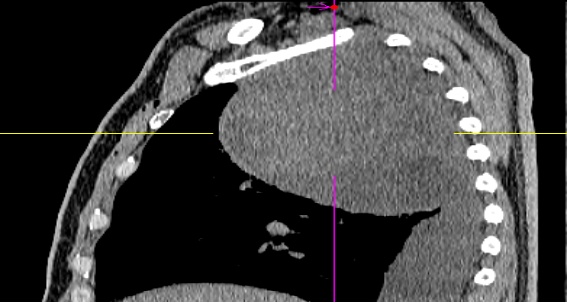

患者黄某因近3个月来反复咳嗽、久治不愈,前往当地医院就诊。检查结果让他和家人大吃一惊:右侧胸腔内竟长有一个巨大的肿块。胸部增强CT显示肿块大小约16cm×12cm,且与胸膜顶大血管关系极为密切。

正月初八,患者慕名来到郴州市第一人民医院东院胸部肿瘤外科就诊。接诊的胸部肿瘤外科主任马忠厦博士分析认为,患者肿瘤巨大,紧贴无名静脉及锁骨下动静脉,手术过程中稍有不慎便可能导致难以控制的大出血,甚至引发失血性休克或心脏骤停。这场手术,堪称在刀尖上起舞。

手术前一天,胸部肿瘤外科牵头组织了由放射科、麻醉科、手术室、病理科、胸部肿瘤内科组成的多学科团队(MDT)进行全院大会诊。专家们通过三维重建技术对患者的影像资料进行精确评估,精准锁定肿瘤与血管及重要脏器的解剖关系,并针对手术中可能出现的三大难点制定了周密预案: